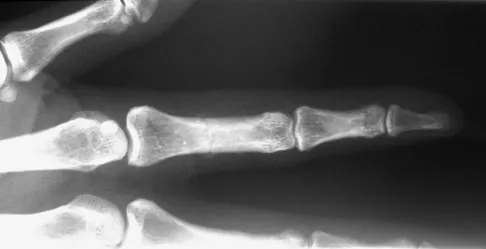

A 47-year-old woman falls and sustains a direct blow to her middle finger. She notes pain and swelling and is unable to move the proximal interphalangeal (PIP) or distal interphalangeal (DIP) joints. Radiographs are shown in Figures 8a through 8c. Proper management should consist of

The oblique nature of the fracture and extension of the fracture to the condyles implies an unstable fracture. Lag screw fixation provides an excellent chance of union, and the ability to start early range of motion. Stern PJ: Fractures of the metacarpals and phalanges, in Green DP, Hotchkiss RN, Pederson WC, et al (eds): Green's Operative Hand Surgery, ed 5. Philadelphia, PA, Elsevier, 2005, p 281.